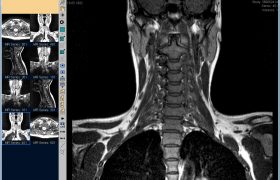

Дорого ли делать МРТ шейного отдела позвоночника: цена в СПб

Раньше сканирование на томографе назначалось крайне редко, что было связано с малой доступностью диагностической процедуры. Исследованием занимались только специализированные клиники, работающие в единичном порядке. Сейчас число центров томографии возросло настолько, что покрывает потребности населения в каждом районе города, поэтому каждый житель Санкт-Петербурга может рядом с домом пройти любые виды томографии, в том числе МРТ шейного отдела позвоночника. Цена в СПб в разных организациях отличается, но градируется не сильно, что зависит от объективных причин